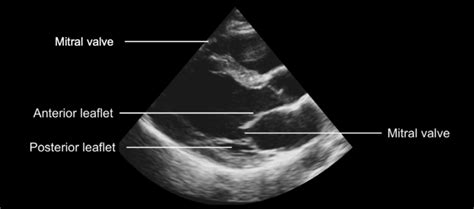

Hey guys, let’s dive into something super interesting in the world of medical imaging: the hockey stick mitral valve echo . You’ve probably heard this term thrown around if you’re dealing with echocardiograms or cardiac conditions, and it’s a pretty cool visual descriptor that helps doctors understand what’s going on with the mitral valve. Basically, when we talk about a hockey stick mitral valve echo , we’re referring to a specific appearance of the mitral valve leaflets on an echocardiogram, especially during diastole (when the heart is relaxing and filling with blood). Imagine a hockey stick, right? It’s got that long shaft and a curved blade. In echocardiography, this shape refers to the anterior mitral valve leaflet. Normally, this leaflet should move quite freely and widely open to allow blood to flow from the left atrium into the left ventricle. However, when it takes on that hockey stick appearance, it means the leaflet is restricted in its movement, often appearing elongated and curved, much like the stick itself. This restriction isn’t just for show; it signifies an underlying issue with the valve’s function. The most common culprit behind this specific echo finding is hypertrophic cardiomyopathy (HCM) , a condition where the heart muscle, particularly the left ventricle, becomes abnormally thick. This thickening can distort the normal anatomy of the mitral valve and its supporting structures. In HCM, the thickened septum (the wall between the ventricles) can encroach upon the space where the mitral valve should open, leading to abnormal blood flow dynamics. The anterior mitral valve leaflet, in response to this altered flow and the proximity of the thickened septum, gets ‘sucked’ or pulled towards the septum during diastole. This abnormal motion creates the characteristic hockey stick shape seen on the echo. So, when your cardiologist says they see a hockey stick mitral valve echo , they’re essentially telling you that they’ve observed this specific, abnormal leaflet motion which is a strong indicator of hypertrophic cardiomyopathy or other conditions that cause similar dynamic obstruction. It’s a crucial piece of the diagnostic puzzle, helping them pinpoint the cause of symptoms like shortness of breath, chest pain, or palpitations that patients might be experiencing. The visualization is key here, and echocardiography is brilliant at providing these dynamic, real-time images of the heart’s intricate workings. Understanding this visual cue allows for a more accurate diagnosis and, consequently, a tailored treatment plan for the patient. We’ll delve deeper into why this happens and what it means for your health.

Alright, let’s get a bit more technical, guys, but still keep it super understandable. So, why exactly does that mitral valve leaflet look like a hockey stick on the echo? It all boils down to the hemodynamics and anatomy changes associated with certain heart conditions, primarily hypertrophic cardiomyopathy (HCM). In HCM, remember, the heart muscle, especially the interventricular septum (the wall between your left and right ventricles), gets really thick. This thickening isn’t uniform; it can be more pronounced in certain areas. Now, think about the mitral valve. It’s designed to open wide during diastole to let blood flood into the left ventricle. The anterior leaflet, the one we’re focused on, is quite large and mobile. When the septum becomes excessively thick, it bulges inwards towards the left ventricular cavity. During diastole, as the left ventricle fills, the pressure changes. Crucially, in HCM, there’s often a phenomenon called dynamic left ventricular outflow tract (LVOT) obstruction . This means that the thickened septum and sometimes other structures can narrow the pathway where blood exits the left ventricle. As blood tries to flow through this narrowed area, it creates a jetting effect, and this altered blood flow pattern is super important. The anterior mitral valve leaflet, being highly mobile, gets caught up in this abnormal flow. It’s kind of like a flag in a strong wind. Instead of opening freely, it gets pulled or ‘sucked’ towards the abnormally positioned, thickened septum. This pulling action causes the leaflet to adopt that characteristic elongated, curved shape – the hockey stick appearance. It’s not that the leaflet itself is intrinsically abnormal in its structure (though sometimes it can be), but rather its motion is dramatically altered due to the surrounding abnormal anatomy and pressure gradients. This dynamic pulling can even cause the mitral valve to partially close during diastole, hindering the heart’s ability to fill properly. This reduced filling can lead to symptoms like shortness of breath because the heart can’t pump enough oxygenated blood to the body. The echo machine, with its sound waves, creates detailed images of these movements. The specific way the anterior leaflet moves and its position relative to the septum during the cardiac cycle is what the echocardiographer looks for to identify this pattern. It’s a direct visual clue that something is causing this abnormal flow and leaflet behavior. So, it’s a consequence of the disease process, a visual manifestation of the mechanical chaos happening inside the heart due to the thickened muscle and altered blood flow. This understanding is vital because it guides the physician in confirming the diagnosis of HCM and assessing the severity of the potential obstruction.

Guys, let’s talk about the unsung hero in detecting that hockey stick mitral valve echo : echocardiography . This imaging technique is absolutely critical, and honestly, it’s the gold standard for visualizing this specific abnormality. Echocardiography, or ‘echo’ as we commonly call it, uses high-frequency sound waves to create real-time images of your heart. Think of it like sonar for your heart! A technician, usually called a sonographer, places a transducer (a wand-like device) on your chest, and these sound waves bounce off the different structures of your heart – the chambers, the walls, and of course, the valves. The echoes are then processed by a computer to build detailed pictures and even moving images of your heart in action. For detecting the hockey stick mitral valve echo , echocardiography is invaluable because it allows us to see the dynamic motion of the mitral valve leaflets throughout the cardiac cycle. We’re not just looking at a static picture; we’re watching how the anterior mitral valve leaflet moves as the heart beats. In a healthy heart, this leaflet opens widely and gracefully during diastole to allow blood flow. However, in conditions like hypertrophic cardiomyopathy (HCM), the thickened septum pushes into the ventricular cavity. The echocardiogram clearly shows how this abnormal anatomy affects the leaflet’s movement. We can visually track the anterior leaflet being drawn towards the thickened septum, creating that characteristic elongated, curved, ‘hockey stick’ shape. Different views within the echocardiogram, like the parasternal long-axis view, are particularly useful for observing this phenomenon. Doppler ultrasound, another component of echocardiography, can also assess blood flow patterns. It can help quantify the degree of left ventricular outflow tract (LVOT) obstruction that often accompanies the hockey stick mitral valve appearance. This helps the doctor understand the severity of the condition and its impact on blood flow. The diagnostic power of echo is immense. It can differentiate between various causes of heart conditions, assess the extent of muscle thickening, measure chamber sizes, and evaluate overall heart function. When it comes to the hockey stick mitral valve echo , it’s a very specific sign that guides the clinician towards a diagnosis of HCM or similar obstructive conditions. Without echocardiography, identifying this subtle yet significant dynamic abnormality would be incredibly difficult, if not impossible. It’s a non-invasive, readily available, and highly informative tool that provides a window into the intricate mechanics of the heart, allowing for precise diagnosis and effective management planning. So, next time you hear about an echo, remember it’s a sophisticated piece of technology doing some truly amazing work, especially when it comes to spotting signs like the hockey stick mitral valve.